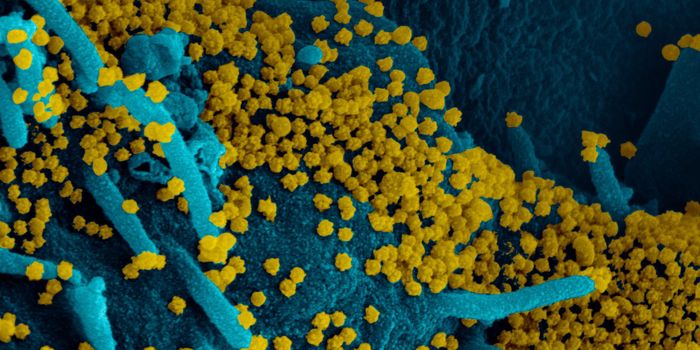

MAR 20, 2020Drug Discovery & DevelopmentCurrently, no medicine nor vaccine has been approved as effective for the prevention of severe acute respiratory syndrom ...

APR 01, 2020ImmunologyScientists have discovered a previously unknown subset of immune cells residing in the lung that specifically com ...

APR 20, 2020Cell & Molecular BiologyThe SARS-CoV-2 virus causea huge range of symptoms, and researchers are learning more about the worst cases, which may h ...